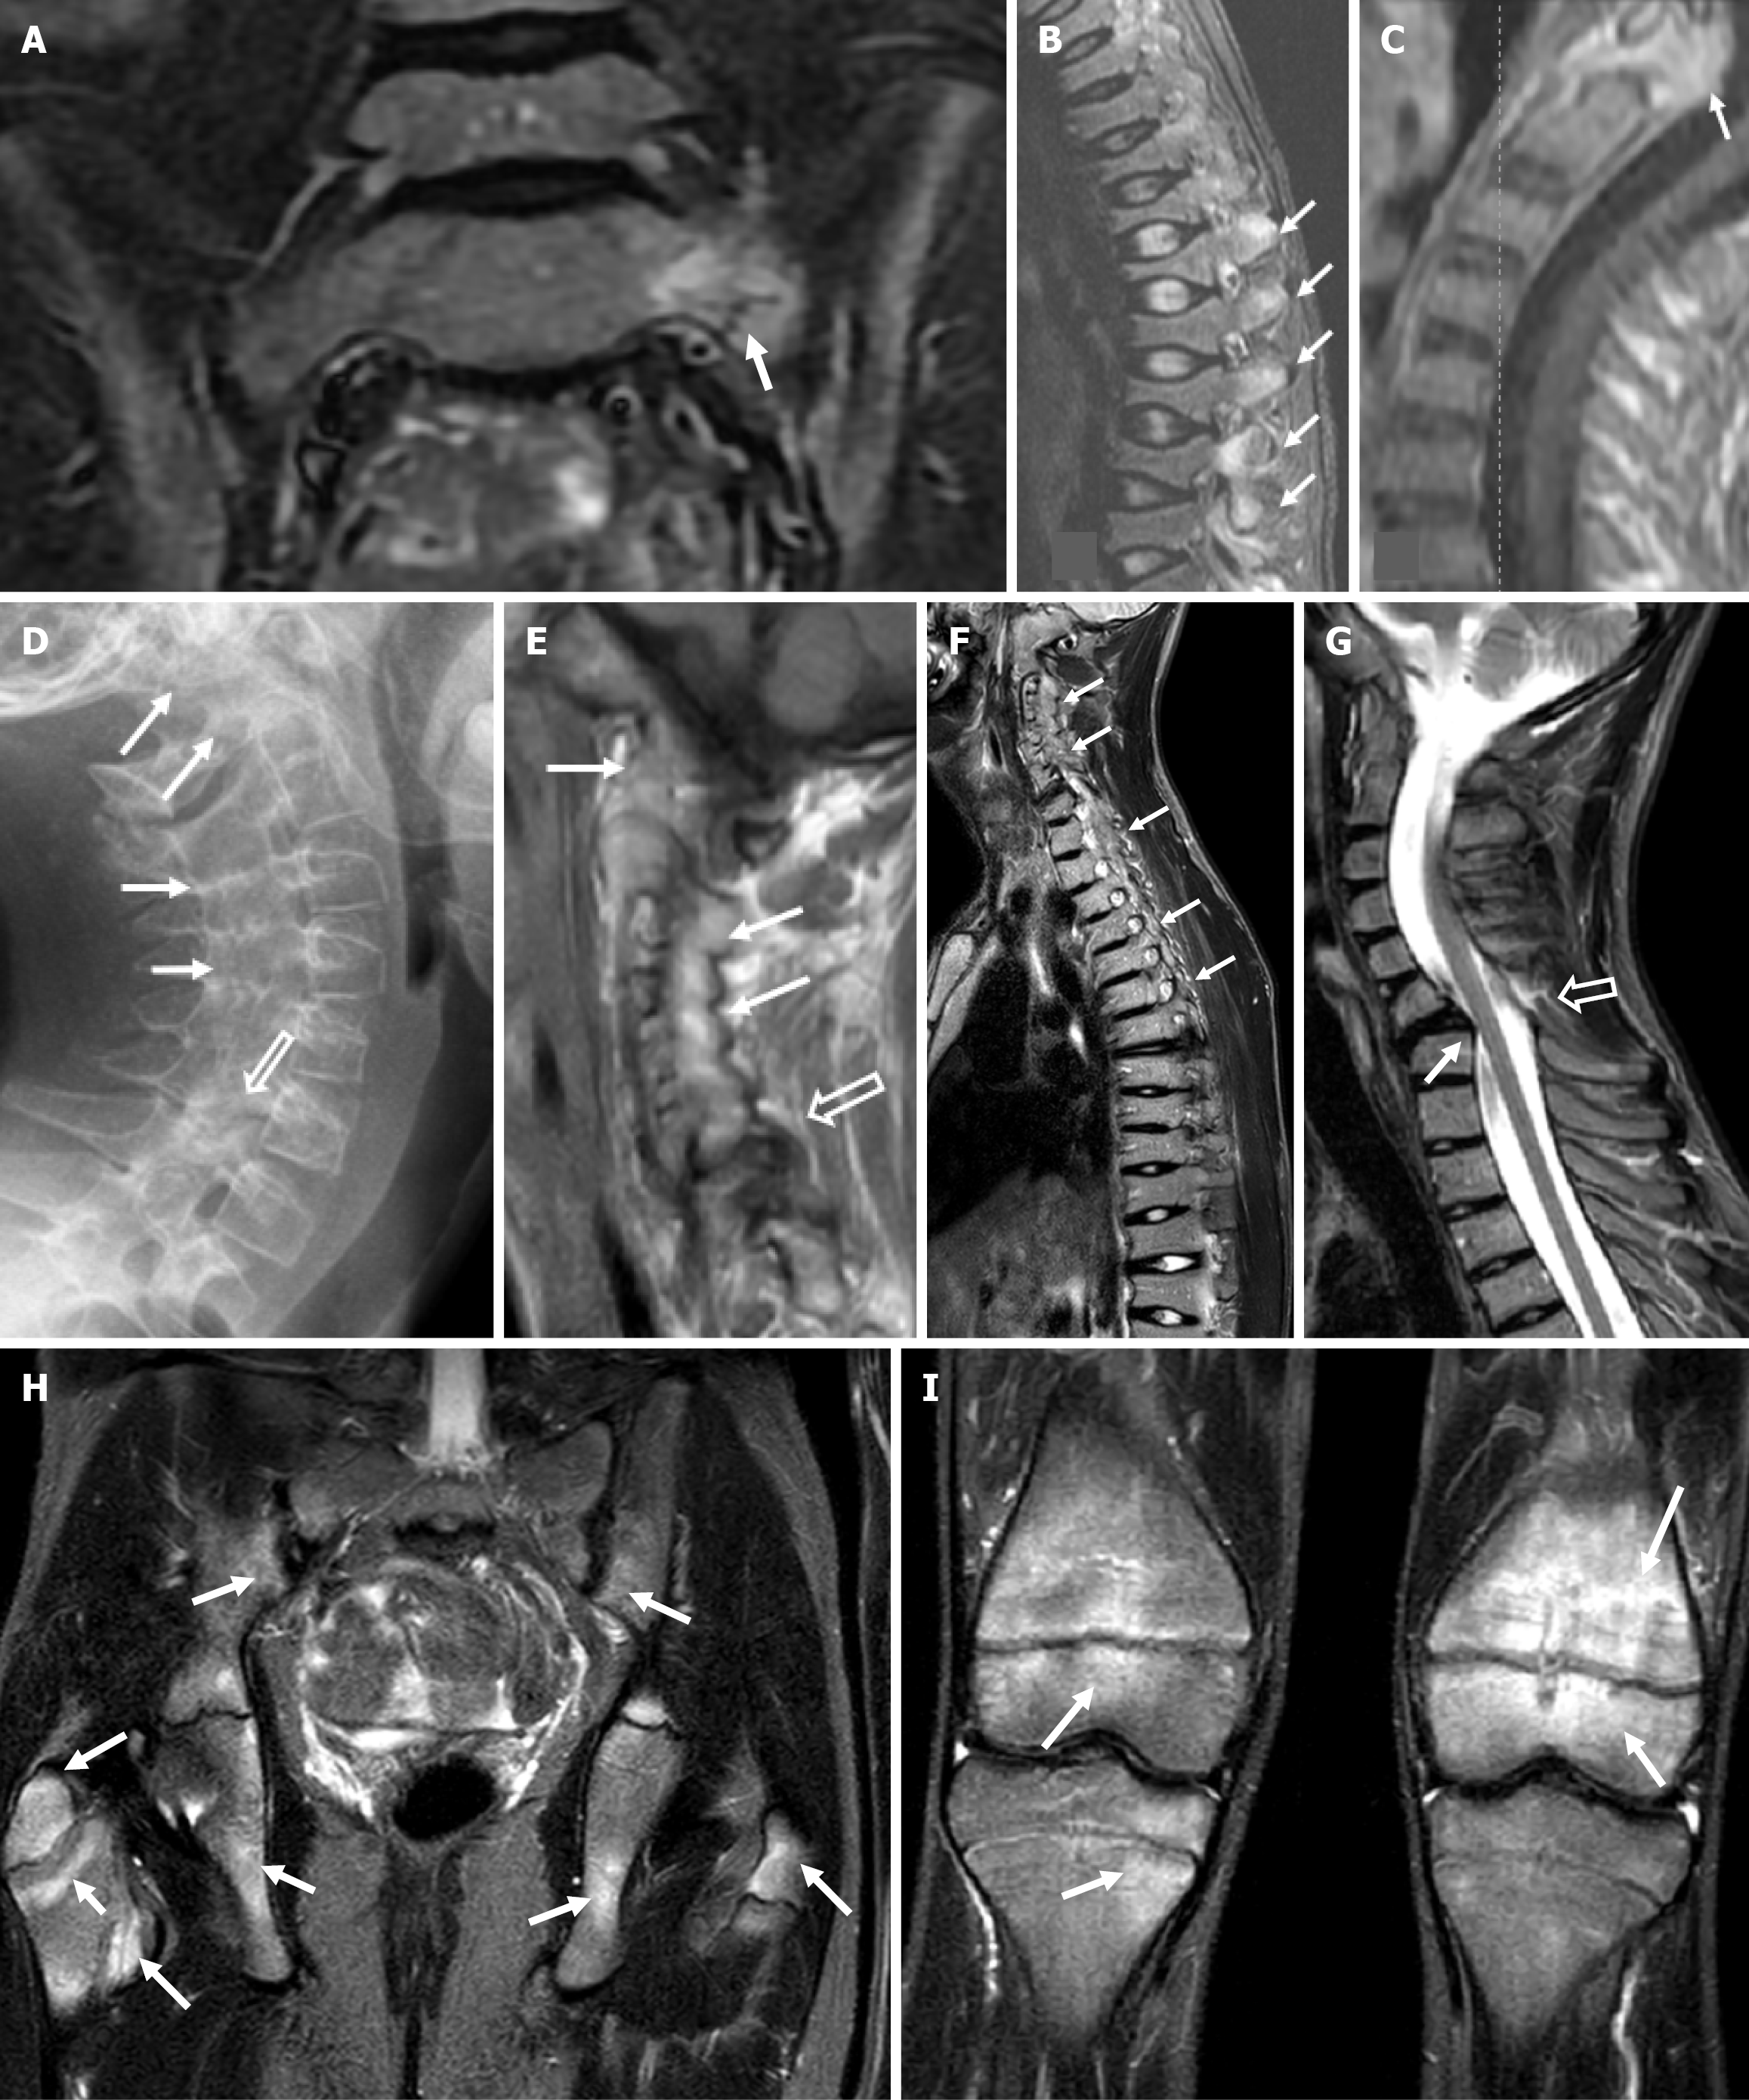

At age 7, an initial magnetic resonance imaging (MRI) performed for low-back pain revealed BME on the iliac side of the sacroiliac joint and a small stress fracture of the left sacral wing, that was initially undetected (Figure 1A).

At age 10, spine MRI demonstrated reduced vertebral height with normal signal intensity of vertebral bodies, multifocal BME of the posterior elements (Figure 1B) and pannus formation around the dens, suggesting inflammatory spondyloarthropathy (Figure 1C).

At age 14, X-ray and spinal MRI showed progressive ossification and fusion of the cervical spine and occiput with pseudoarthrosis at the C6-C7 level (Figure 1D and E). Bisphosphonate and anti-inflammatory therapy were administered.

WB-MRI, performed at age 15, for diffuse skeletal pain demonstrated further progression of fusion of posterior elements of the spine (Figure 1F), prolapse of the C6-C7 intervertebral disk, at the level of pseudoarthrosis (Figure 1G) and levoscoliosis of the lumbar spine; however BME of the posterior elements had subsided whereas the height of thoracic and lumbar vertebral bodies was significantly restored. In addition, multiple areas of BME in the peripheral skeleton were seen, most of them in periphyseal distribution, suggestive of concomitant chronic non-bacterial osteomyelitis (CNO) (Figure 1H and I).

Repeat WB-MRI at age 16, revealed a global reduction of the inflammatory load with no change of the structural changes after stable structural deformities of the spine.

The longitudinal comparison between WB-MRI at age 15 and age 16 depicted a clear distinction. Active inflammatory lesions, characterized by T2-weighted short tau inversion recovery hyperintensity, demonstrated significant response to therapy. Conversely, structural lesions involving ossification and remodeling showed no regression.